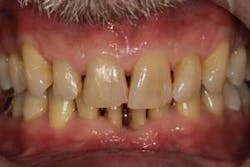

Figure 3: Initial presentation in 2011 of the mandibular anterior sextant, showing advanced hard- and soft-tissue loss.

At presentation, Martin was in his fifties with a medical history significant for controlled hypertension with no known food or drug allergies. He had been lackadaisical with his dental care in the past because of his busy schedule, but he was motivated to get his hygiene and treatment under control. He denied a history of smoking/alcohol/drug use. Based on his full-mouth series (figure 1) and clinical presentation, Martin had generalized, moderate bone loss with localized, severe bone loss in the posterior maxillary right and left quadrants (figures 2a and 2b) as well as the mandibular anterior incisor area (figure 3).